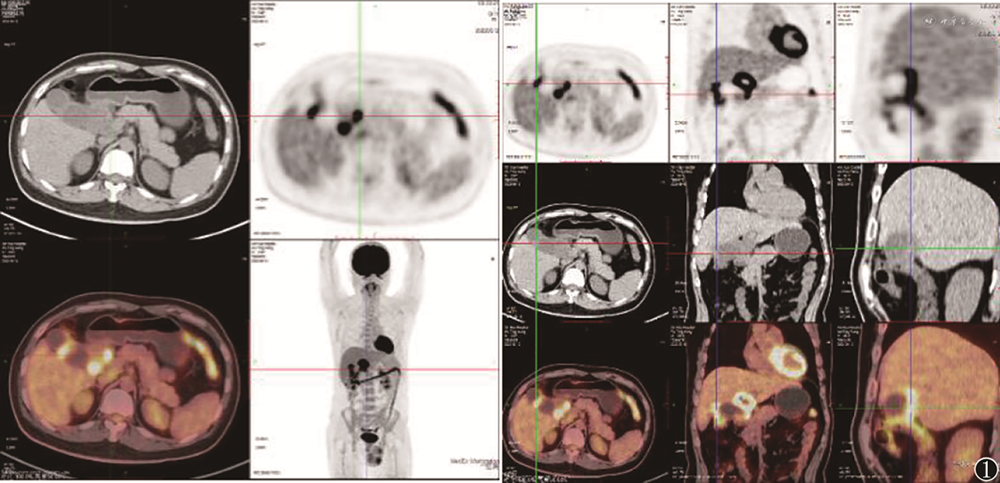

患者男,34岁,因“上腹部疼痛2月余”入院。入院前2月余饱餐后出现中上腹钝痛,疼痛呈进行性加重,无恶心、呕吐、呕血、腹胀、皮肤瘙痒等不适。外院CT示肝门部囊状病变伴肝内胆管扩张,胆囊结石。肝功能:总胆红素109.0 µmol/L,碱性磷酸酶380.0 U/L。予以保肝治疗后症状无明显缓解。2个月后复查上腹部CT及MRI均提示:胆囊癌累及邻近肝实质可能。复查肝功能:总胆红素19.8 µmol/L,碱性磷酸酶279.0 U/L。患者为寻求进一步治疗入我院。入院后上腹部增强CT:胆囊壁增厚,肝门区胆管壁增厚,考虑恶性,伴临近肝实质累及,肝内胆管扩张,肝门区淋巴结转移;胆囊结石。PET-CT示:胆囊壁不均性增厚,高代谢改变,考虑胆囊癌,并肝门区转移灶(胆管受累可能),侵及邻近肝脏及结肠,肝门区淋巴结转移(图1)。肝功能:总胆红素8.9 µmol/L,谷氨酰转移酶205.0 U/L,余正常。肿瘤指标正常。查体无殊。初步诊断为:胆囊占位性病变,胆囊结石。多学科讨论认为:行保肝等治疗后患者黄疸及肝功能好转,肿瘤标志物未见明显异常,临床表现与恶性肿瘤不符,但患者影像学表现提示胆囊癌并发胆管癌可能性大,PET-CT提示胆囊癌,并肝门区转移灶(胆管受累可能),侵及邻近肝脏及结肠,肝门区淋巴结转移。患者为年轻男性,建议行超声引导下穿刺或腹腔镜下活检明确病理,根据病理结果决定下一步治疗方案,如为恶性,建议行新辅助化疗后行手术切除。遂行超声引导下病理穿刺,因肝门区界限不清,穿刺损伤胆管风险较大,中止操作。完善术前检查后行腹腔镜探查术,腔镜下见胆囊大小约8 cm×6 cm×4 cm,胆囊三角欠清晰,与邻近组织粘连致密,肝十二指肠韧带与大网膜粘连致密。行开腹探查术,取上腹部正中切口,经解剖后,见胆囊三角粘连致密,解剖肝十二指肠韧带,见肝4b段直径3 cm大小脓肿,打开脓肿吸出大量脓液,冲洗脓腔,探查脓腔与胆道不相通,决定对肝脓肿仅行切开引流。游离胆囊底体部至胆囊管,缝扎胆囊管开口,切除胆囊。胆囊床电凝止血。取出标本,见胆囊内结石数枚。术中冰冻病理:黄色肉芽肿胆囊炎。术后病理:黄色肉芽肿胆囊炎。术后恢复可,终至出院。